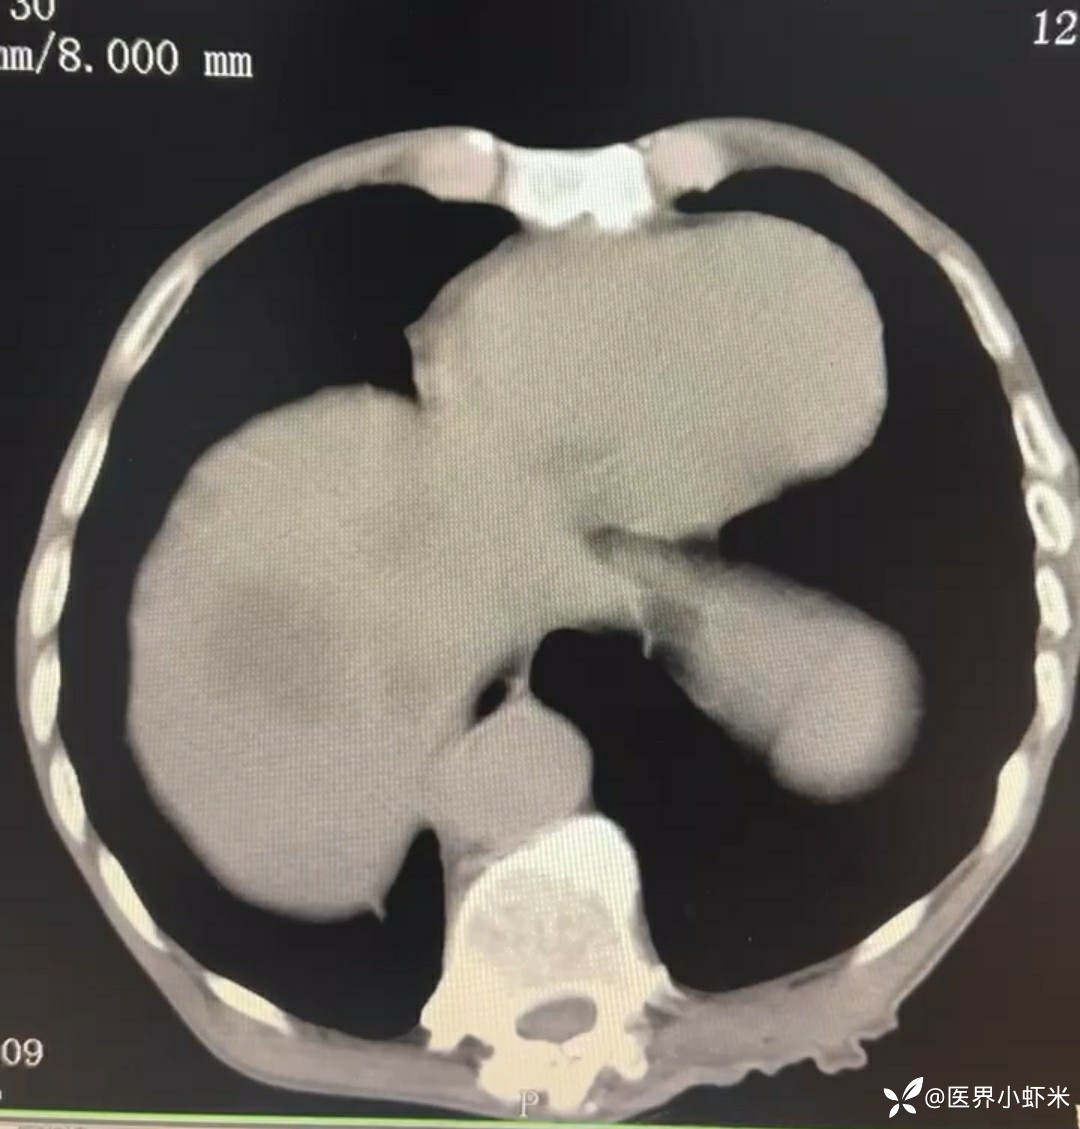

目前考虑:1.中央型肺癌伴2.肝继发恶性肿瘤?2.左丘脑继发恶性肿瘤?3.左丘脑出血?4.肾功能不全5.肝功能异常6右肾萎缩7.肺部感染8.慢性阻塞性肺病7.高血压3级(极高危)。